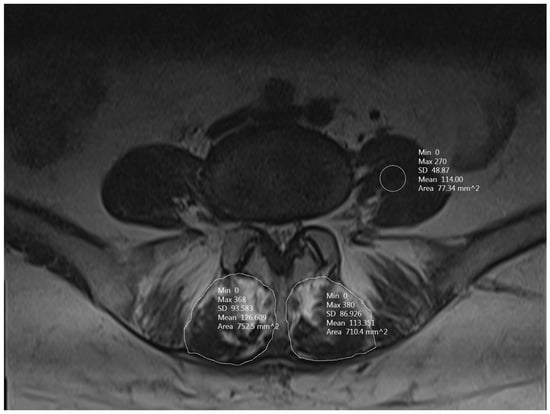

2.3. Radiological Evaluation

3.4. MFM CSA